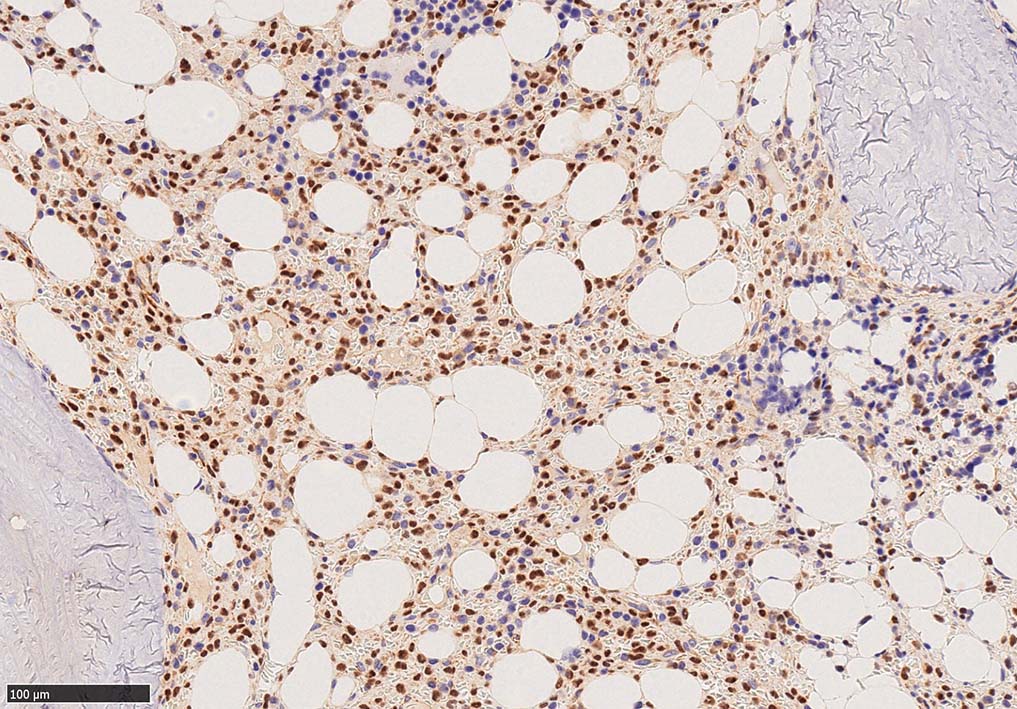

Hairy-FCM のコピー.jpg ASD-up-PAX5ok.jpg びまん性にPAX5陽性の小型B-cellsが増殖している.

増殖細胞はCD20(相変わらずべったり染まる), CD19, PAX5陽性 CD25陽性.

BRAF V600E変異タンパクの免疫染色(山梨医大 大石先生に染色していただきました. ベンタナ, Optiview)